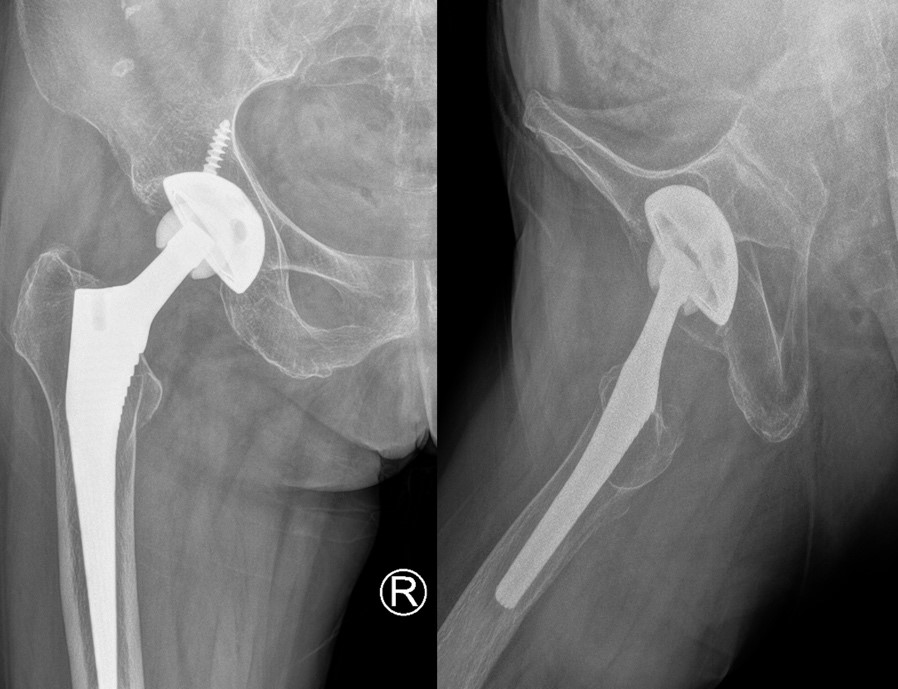

由于距离初次手术已有14年之久,原先的影像资料都已丢失,加之张女士较为年长合并有高血压、脑梗塞、长期疼痛导致失眠及骨质疏松症等诸多问题。因此,髋关节翻修手术较初次置换手术难度与风险都要高得多。在入院完成一系列检查后,由骨科姜为民主任医师、林俊主任医师、王亮副主任医师带头,为张女士制定了周密的手术方案,分析了术中的难点以及可能出现的问题和应对措施。同时,骨科联合麻醉科、输血科、重症医学科、康复医学科等科室,进行术前多学科评估,确保手术安全进行。在全身麻醉下手术正式开始,术中顺利取出角度不良且已磨损的髋臼假体。随后,将臼杯重新置于正确位置后打实固定,更换假体股骨头,并使下肢长度恢复一致。整个手术过程历时三个小时最终顺利结束,术后在张霞芬护士长带领的护理团队精心护理下张女士恢复良好。

翻修术后复查X线片提示髋臼侧假体外展角及前倾角理想,两下肢等长